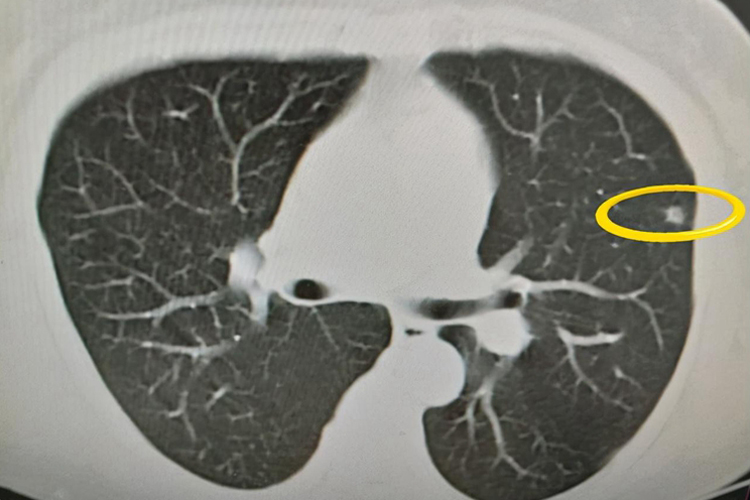

- 磨玻璃结节密度增高,可能提示病变有进展、恶变倾向或已经恶变,比如早期肺癌的磨玻璃结节,在随访过程中如果发现密度逐渐增高,往往提示恶性程度增加。

- 但判断磨玻璃结节的性质和风险不能仅依据密度这一项指标,还需要考虑结节的大小、形态、边缘特征、内部结构、有无分叶、毛刺、空泡征、胸膜牵拉征,以及患者的年龄、吸烟史、家族史、肿瘤标志物水平和结节的动态变化等因素。